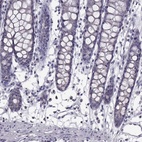

Immunohistochemistry analysis in human esophagus and colon tissues using Anti-ALDH3A1 antibody. Corresponding ALDH3A1 RNA-seq data are presented for the same tissues.